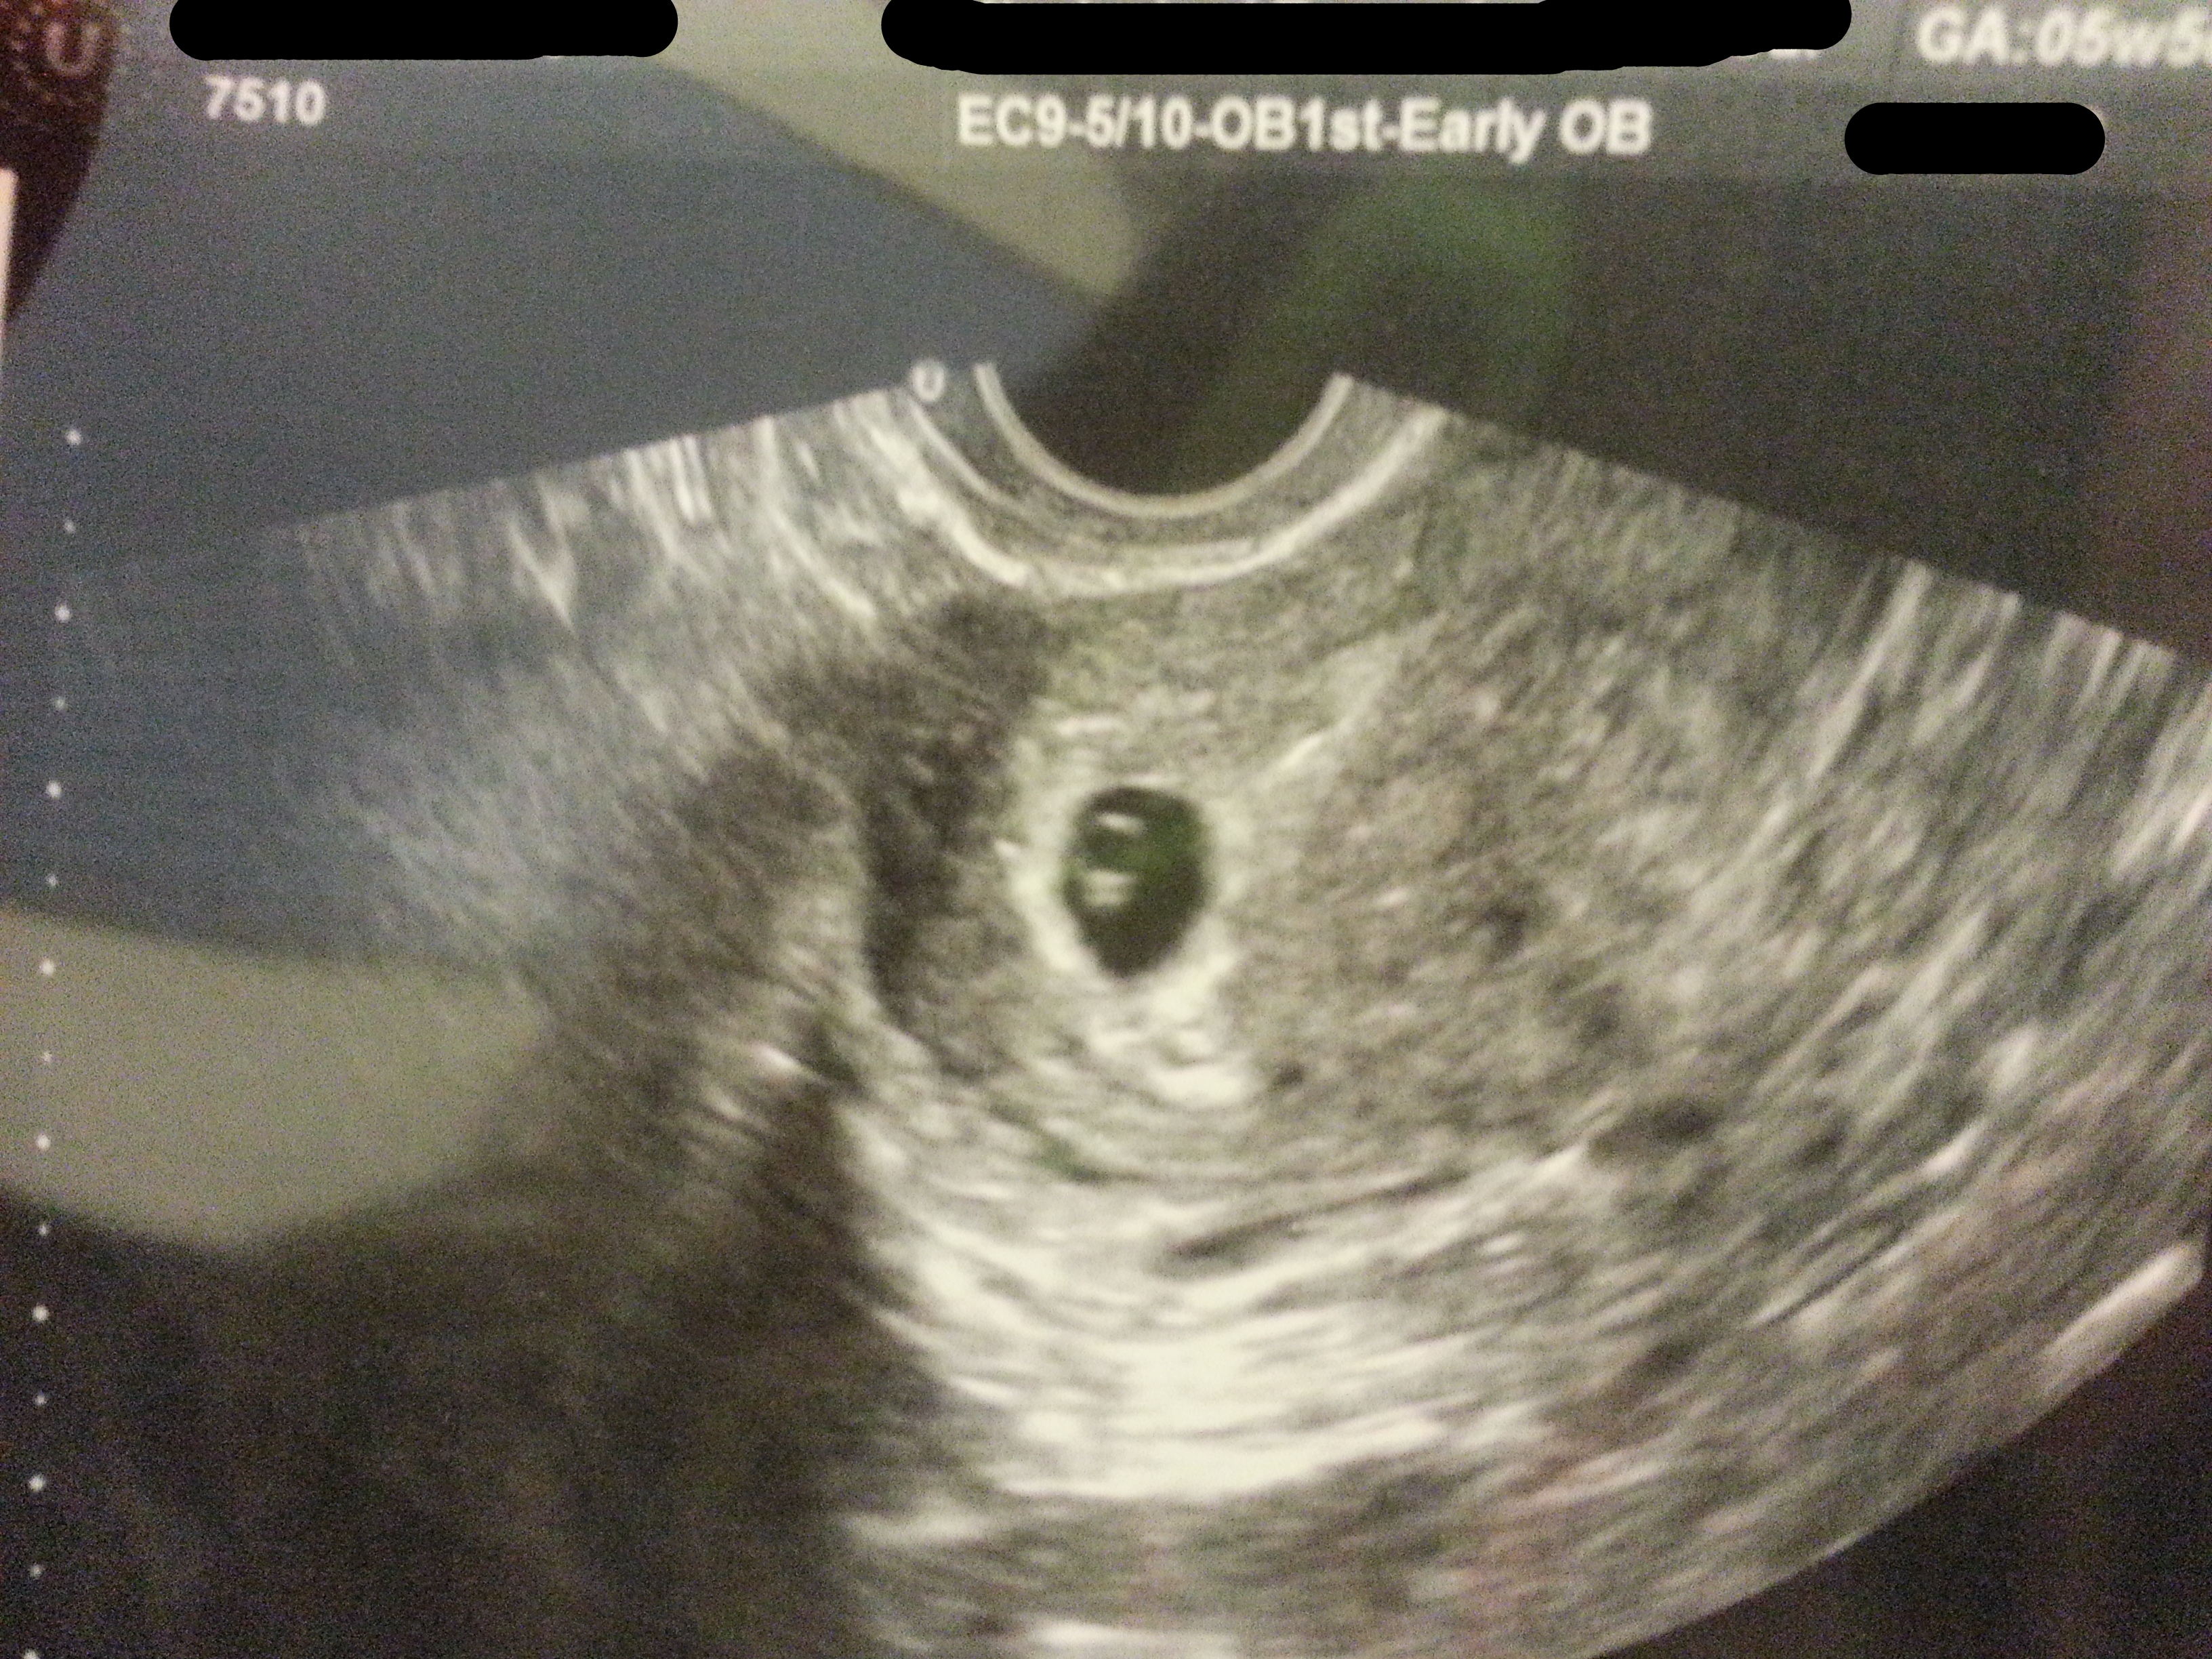

here are 2 US's (done at same time) of my first child at 5 wks 5 days and hr was 96.15 (guess what it was :))

Attachment 22519

They were both T/V but first pic was done by my OB and the other 2 pic are done by a specialist since that was my 6th pregnancy.